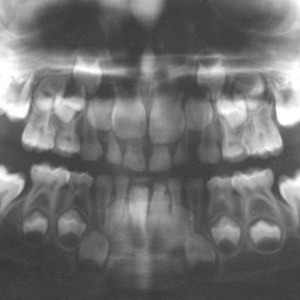

A panoramic radiograph is a panoramic scanning dental X-ray of the upper and lower jaw. It shows a two-dimensional view of a half-circle from ear to ear.

The X-rays use small amounts of radiation. Panoramic X-rays show a broad view of the jaws, teeth, sinuses, nasal area, and temporomandibular (jaw) joints. These X-rays show problems such as impacted teeth, bone abnormalities, cysts, solid growths (tumors), infections, and fractures